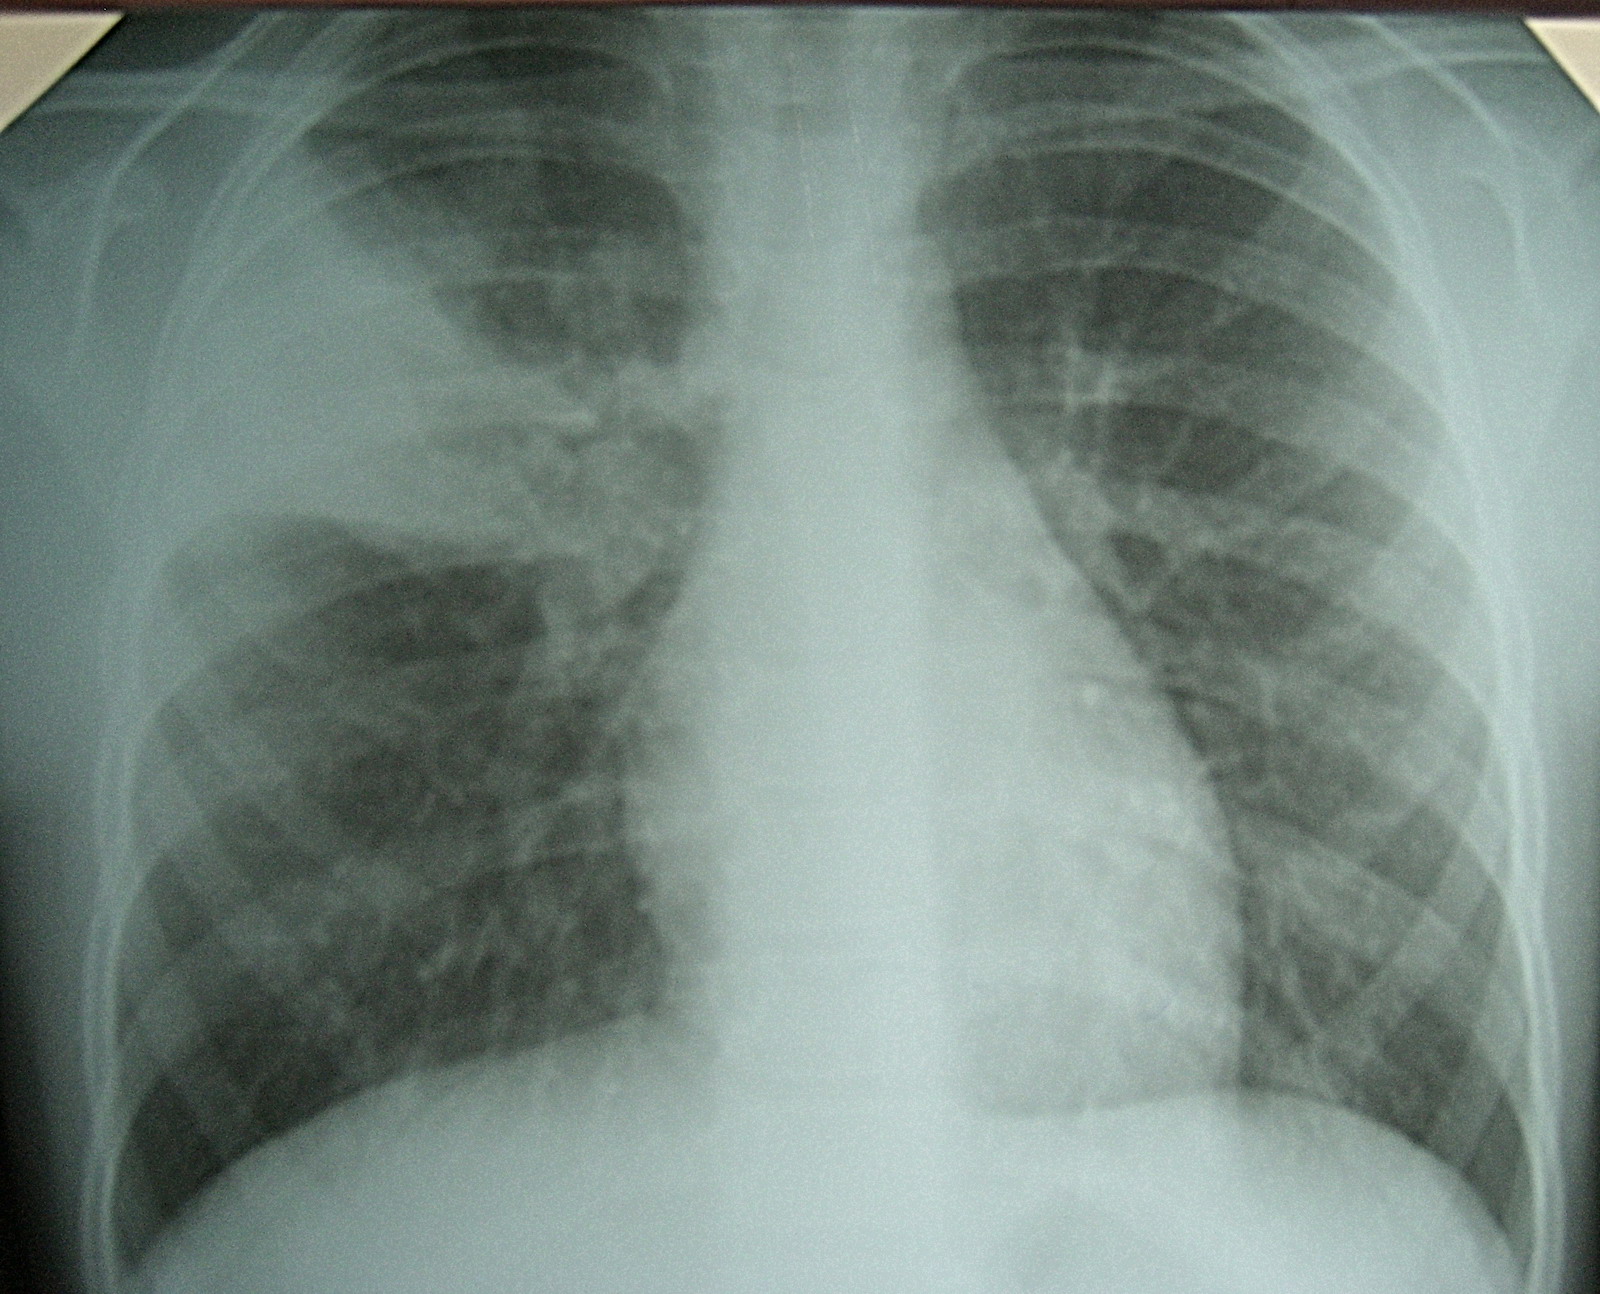

Сергей Авдеев: Нынешняя атипичная пневмония, она же вирусная пневмония, действительно отличается от внебольничной пневмонии, с которой мы имели дело раньше. Хотя вирусные пневмонии известны нам достаточно давно. Вспомните пандемию гриппа h2N1. Но пневмония, связанная с новым коронавирусом, протекает необычно. Это связано с тем, что у пациентов с COVID-19 мы наблюдаем самые разные степени повреждения легких с абсолютно разными клиническими проявлениями. Например, появились пациенты, у которых подтвержден новый коронавирус лабораторными тестами.

Но у которых нет абсолютно никаких жалоб, симптомов и признаков болезни. Нет ни лихорадки, ни кашля, ни одышки. При этом при проведении компьютерной томографии у пациентов обнаруживаются признаки пневмонии. Приведу в пример историю с круизным лайнером «Diamond Princess». Как вы помните, на борту этого судна была высокая заболеваемость коронавирусной инфекцией. Некоторые пациенты проходили обследование с помощью компьютерной томографии легких. Обнаружилось, что у 73% больных с лабораторно подтвержденной коронавирусной инфекцией не было абсолютно никаких симптомов. Среди этих же бессимптомных пациентов на компьютерной томографии легких были изменения, говорящие о наличии пневмонии. Они были выявлены у 54% больных. То есть у подавляющего большинства. Это значит, что мы сегодня столкнулись с фактом возможности развития абсолютно бессимптомных форм пневмоний.

Основная причина госпитализации у большинства наших больных — как раз развитие вирусной пневмонии. У пациентов, госпитализированных в стационар, мы практически в 95-100% случаев видим изменения, соответствующие пневмонии. Изменения разные, в том числе и очень тяжелые. Одна из особенностей вирусной пневмонии — быстрое прогрессирование, вплоть до развития острого респираторного дистресс-синдрома. Это тяжелое состояние, характеризующееся острой дыхательной недостаточностью, требующее перевода пациентов на респираторную поддержку. В том числе и на искусственную вентиляцию легких. Примерно 10% больных от госпитализированных нуждаются в такой процедуре.

Сергей Авдеев: Да, безусловно. Сегодня большой акцент делается на компьютерной томографии легких. Этот метод относится к имидж-диагностике, как и рентгенография. Но компьютерная томография — более точная и специфичная методика выявления изменений в ткани легких по сравнению с обычной рентгенографией. Большинству пациентов с COVID-19 как раз и требуется такая методика. Компьютерную томографию я бы поставил сегодня на первое место среди всех имеющихся методов для подтверждения диагноза. По своей чувствительности она даже превосходит лабораторную диагностику для подтверждения вирусной инфекции. Чувствительность компьютерной томографии превышает 90%.

Сергей Авдеев: Да, отличия существенные. При COVID-19 практически всегда пневмония двусторонняя, расположена по периферии легких (под плевральной оболочкой). На начальных этапах она имеет вид, как говорят рентгенологи, «матового стекла». При прогрессировании изменения становятся более плотными и распространенными. А затем происходит фаза обратного развития — уменьшение размера и плотности легочных инфильтратов.

Сергей Авдеев: Это абсолютно новая болезнь для нас. Данная вирусная инфекция имеет огромный тропизм (свойство действовать на ткани и клетки определенного типа — прим. «Ленты.ру») к альвеолярному эпителию, то есть мишенью для вируса является легочная ткань. Таких вирусов мы раньше просто не видели и не знали. Сейчас в наших клиниках среди госпитализированных с ковидом пациентов почти у каждого есть пневмония — у 95 процентов! Это очень необычное явление.

Сама пневмония протекает по абсолютно разным сценариям. В ряде случаев — без единого симптома. Ни температуры, ни кашля, ни одышки. То есть человек просто не ощущает, что болеет.

Другой сценарий — пневмонии при COVID-19 часто быстро прогрессируют, у пациентов возникает острая дыхательная недостаточность. Это требует использования сложных методов респираторной поддержки, включая искусственную вентиляцию легких.

Да, это одна из особенностей COVID-19. Самый действенный метод — увидеть пневмонию на компьютерной томографии. Чувствительность метода КТ достигает 97 процентов, поэтому он выходит на первый план при диагностике воспалительного процесса.

Если коротко, то при COVID-19 пневмония — двусторонняя, локализация — периферическая. Микоплазменные пневмонии чаще односторонние. Встречаются и двусторонние, однако в этом случае томографические снимки отличаются, изменения в легких иные.

Наши рентгенологи, описывая снимки легких при ковидных пневмониях, употребляют такие термины, как «булыжная мостовая», симптом «матового стекла». Именно так выглядят поражения

Одно из главных отличий вирусной пневмонии от бактериальной – быстротечность. Ковидное воспаление легких протекает стремительно и агрессивно

Одно из главных отличий вирусной пневмонии от бактериальной – быстротечность. Ковидное воспаление легких протекает стремительно и агрессивно, быстро наступает дыхательная недостаточность.

Если для развития бактериальной пневмонии требуется время – неделя, а то и две, то для вирусной достаточно четырех-пяти дней от начала заболевания. При этом симптомов может не быть вовсе, объясняет пульмонолог.

Бактериальной пневмонии всегда предшествует яркая симптоматика, при ковидной изменения в легких могут опережать симптомы. Человек может чувствовать себя вполне нормально, а часть легких у него уже поражена.

Рентгенологи делят ковидную вирусную пневмонию на четыре стадии, в зависимости от объема поражения легких: это кт-1 (легкая), кт-2 (среднетяжелая), кт-3 (тяжелая) и кт-4 (критическая).

КТ на ранней стадии позволяет увидеть те изменения, которые называются синдромом «матового стекла». На снимке видно, что альвеолы как бы затянуты «дымкой». Если бактериальная пневмония проявляется в виде участков уплотнения, очаговых теней, то здесь легкая «дымка» окутывает все ткани альвеол.

Более тяжелые стадии вирусной пневмонии на рентгеновском снимке напоминают, по словам специалиста, «булыжную мостовую».